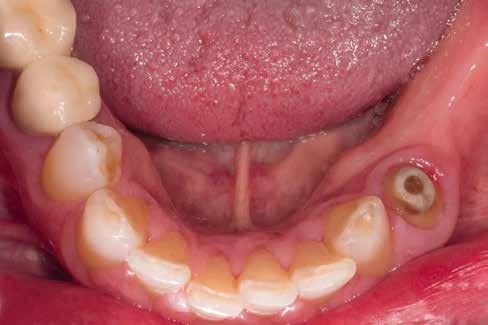

Az eset

A 75 éves páciens új fogsorokat szeretett volna. Felül nem kielégítő teljes lemezes kivehető fogsora volt, alul pedig szintén nem megfelelő részleges fogsora, néhány devitális, apikális oszteolízist és masszív szekunderkárieszt felmutató mutató maradék frontfogon. Az endodonciai beavatkozást a páciens elutasította. Ehelyett kerámiaimplantátumokra alapozott kezelést kívánt. Az úr általános egészségi állapotában panaszok mutatkoztak. A CMD-index nem volt számottevő. A DVT-vizsgálat (1. kép) alapján megállapítható a 42-es fog decens apikális oszteolízise, számottevő vertikális és horizontális csontveszteség a rágóterületen, valamint az

1. kép: Kiindulási helyzet: az OPG hat devitalizált alsó frontfogat ábrázol, részleges apikális oszteolízissel, szekunderkáriesszel, horizontális csontfelszívódással a rágóterületen.

FDOK/NICO értelmében HU alapján mért erőteljes csontsűrűség-csökkenés mutatkozik az 18, 17, 13, 23, 27 és 28 fogak régiójában.